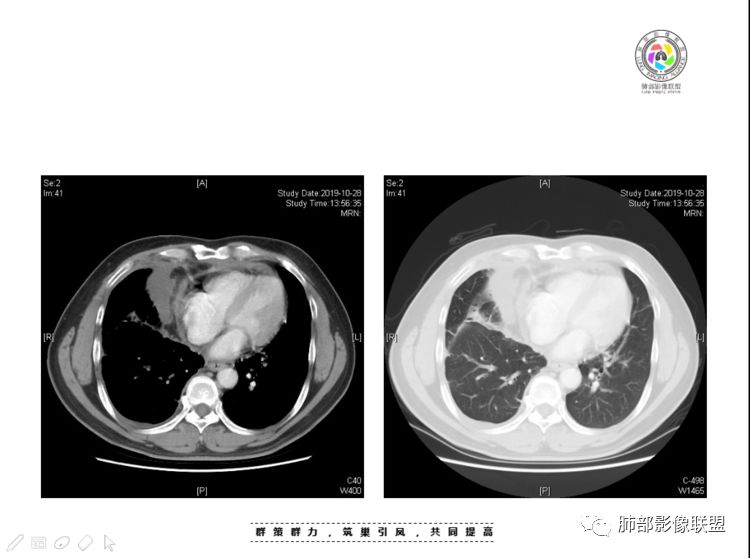

2、前纵隔内病灶囊实性混杂密度病灶,囊性病灶主要位于右侧,张力较高,有分隔影,囊壁右侧缘光整,病灶左侧实性部分边界不清明显强化,病灶肺瘤交界面大部分边界清楚,部分模糊。

纵隔内病灶不符合肺癌转移途径,且纵隔内单发的囊实性转移罕见。淋巴瘤无论是分布、形态、密度、还是强化方式度不符合。

患者缺乏纵隔炎的临床表现,囊性病损更难以解释。

胸腺瘤/胸腺癌符合吗?

胸腺瘤/胸腺癌:病灶内那么大的囊,常规考虑B型以上胸腺瘤,囊内有分隔影,病灶周围脂肪间隙模糊,常规考虑侵袭性胸腺瘤或胸腺癌,若侵袭性胸腺瘤,常侵犯胸膜、心包,很少累及肺。胸腺癌易侵犯胸膜、肺并纵隔淋巴结及远处转移。但肺内腺癌形态更符合原发灶。胸膜及叶间裂转移则即可来自肺,也可来自胸腺癌。